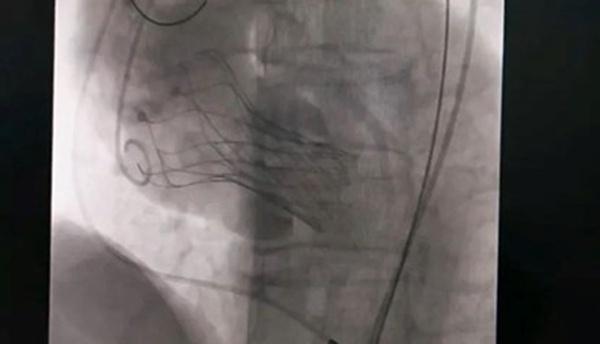

10月18日,該患者實(shí)施手術(shù),在新橋醫(yī)院專家的指導(dǎo)下,心血管內(nèi)科主任宋明寶帶領(lǐng)團(tuán)隊(duì)把瓣膜置入心臟。

人工瓣膜置入中。重慶西區(qū)醫(yī)院供圖